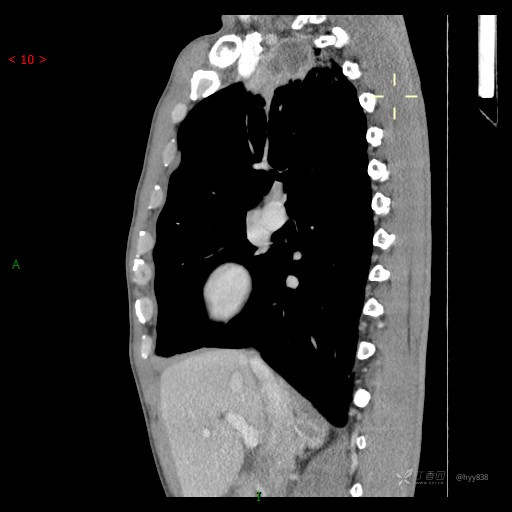

反复发热8天。肺尖区占位,纵隔或肺来源?感染、肿瘤或兼而有之--结果公布(少见)

简要病史:患者自述8天前开始出现寒颤、发热,最高达39℃,自行口服退热药物治疗,每天两次,偶有咳嗽,无明显咳痰,无咯血,无头晕、头痛等不适,诉夜间出汗较多,无乏力、食欲减退等不适,为求进一步治疗于2023.4.2来我院门诊查胸部CT提示右肺尖占位,纵膈淋巴结增大,血常规白细胞升高,为求进一步治疗来院,门诊以“肺占位”收入我科。 患者自起病来,精神、饮食、睡眠可、大小便正常,体重及体力无明显改变。

实验室检查:降钙素原 0.1 ng/ml ,C反应蛋白 79.0 mg/L ↑,白介素-6 44.03 pg/mL ↑,淀粉样蛋白A(SAA) 396.5 mg/L ↑; 血细胞分析 白细胞计数(WBC) 9.25 *10^9/L ,中性粒细胞数(NE#) 7.04 *10^9/L ↑

辅助检查:CT

胸部CT平扫

增强动脉期

静脉期